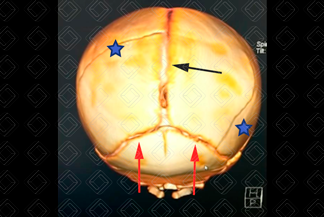

Texto alternativo para a imagem Figura 3. Créditos: Dra. Elazir Mota - Rio de Janeiro/RJ

Descrição da figura 3: Tomografia computadorizada de crânio com reconstrução tridimensional (3D). Dois traços de fratura (asteriscos). As demais linhas alargadas representam as suturas cranianas ainda abertas (comum nos recém-nascidos): sutura sagital (seta preta) e suturas lambdoides (setas vermelhas).

• Tomografia computadorizada do crânio (figuras 1, 2 e 3): Exam e de escolha no cenário de emergência por tratar-se de exame rápido e amplamente disponível. Co leção hiperdensa extra-axial e biconvexa . Deve-se procurar sempre por ar no interior do hematoma, que é um sinal de fratura associada do seio paranasal e mastoide, ou pelo sinal do redemoinho, uma heterogeneidade no interior do hematoma que sugere sangramento ativo. Sempre buscar por fraturas nas reconstruções tridimensionais (3D) e na janela óssea;